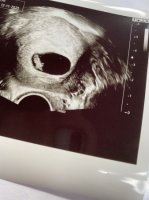

han tok nok flere målinger som i gjennomsnitt gav 6+3, mens denne ene målingen kanskje viste tilsvarende 6+6. I de fleste tilfeller er det uansett menstermin som "teller" frem til ordinær UL

Fikk høre hjertet også- veldig deilig!